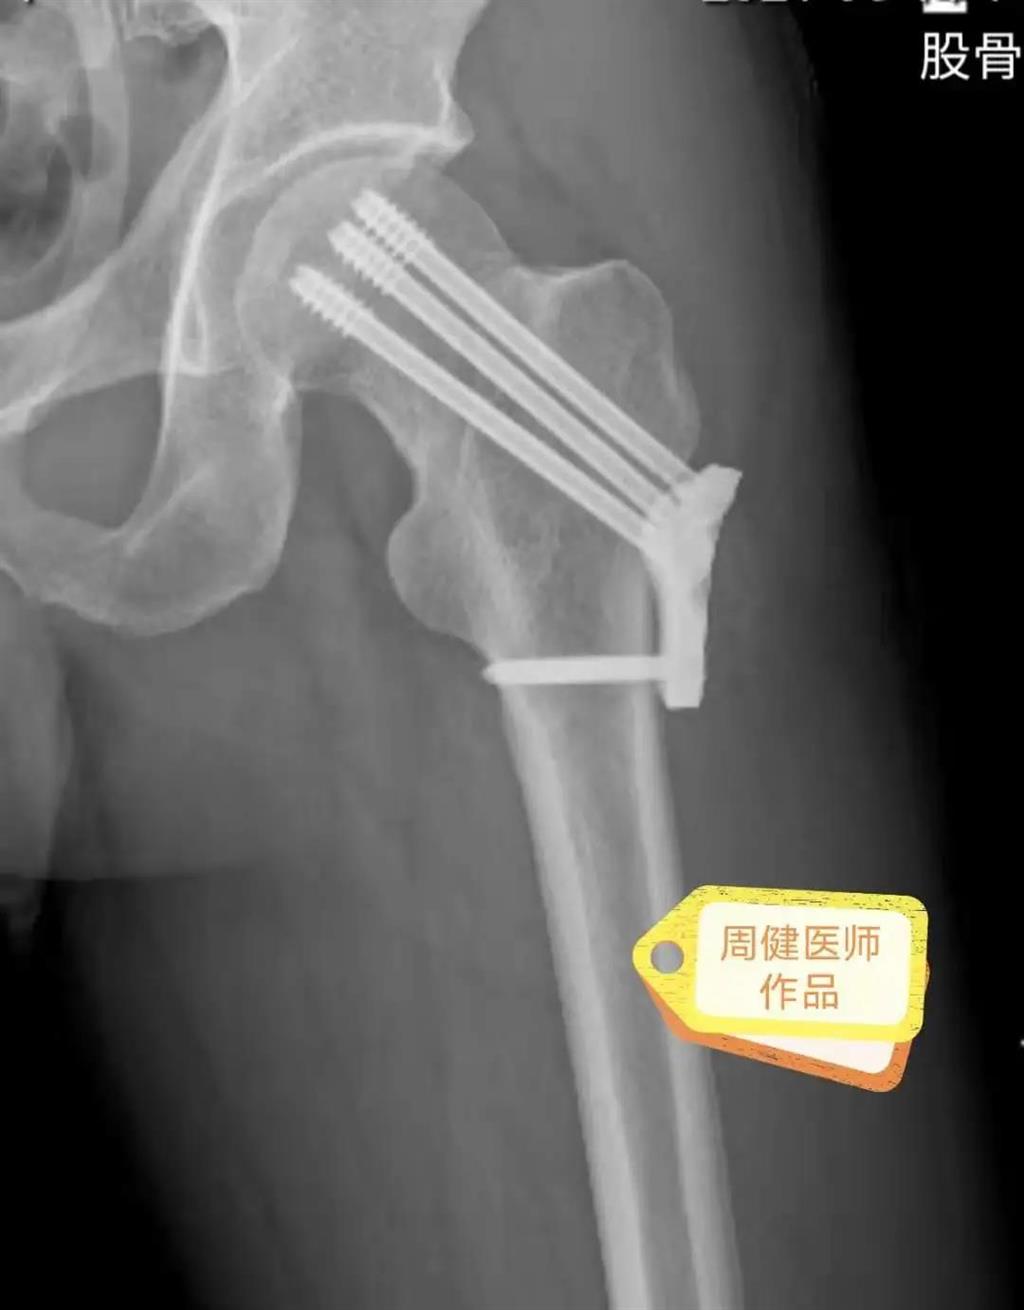

6月30日的“關(guān)節(jié)置換術(shù)”,患者是一位上了年紀(jì)的老人,苦于病痛折磨多年的他四處“求醫(yī)問藥”,最后在多位專家醫(yī)師及病友地力薦下選擇了和平國際醫(yī)院,在醫(yī)師團(tuán)隊(duì)“偷天換日”般的手術(shù)后,老人成功告別了苦纏多年的病痛。

周健說,這場“關(guān)節(jié)置換術(shù)”對(duì)于他們團(tuán)隊(duì)而言其實(shí)算是比較普通的手術(shù),因?yàn)樽鲞^很多同類的手術(shù),成功案例繁多,因此在手術(shù)操作上有較多地實(shí)操經(jīng)驗(yàn)。“不過話雖如此,作為醫(yī)生我們對(duì)于每一場手術(shù)都會(huì)全力以赴,這是為醫(yī)者的職責(zé)也是義務(wù)。”